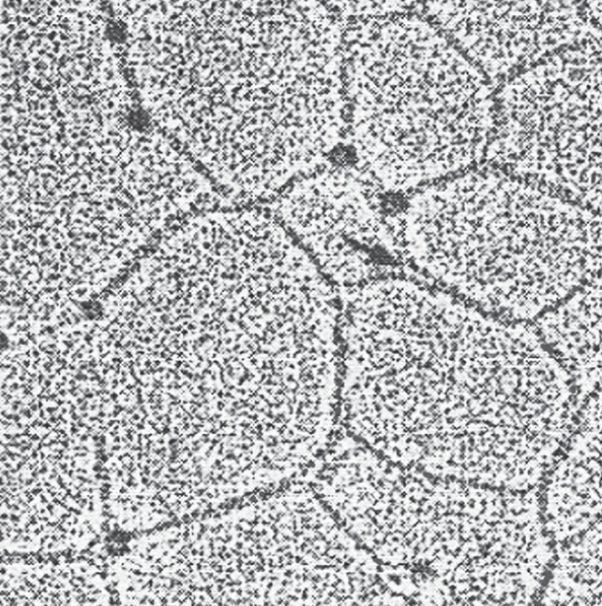

2. Network-forming collagens: Types IV and VIII form a three-dimensional mesh, rather than distinct fibrils (Fig. 3). For example, type IV molecules assemble into a sheet or meshwork that constitutes a major part of basement membranes.

Figure 3: Electron micrograph of a polygonal network formed by association of collagen type IV monomers.

Basement membranes are thin, sheet-like structures that provide mechanical support for adjacent cells and function as a semipermeable filtration barrier to macromolecules in organs such as the kidney and the lung.